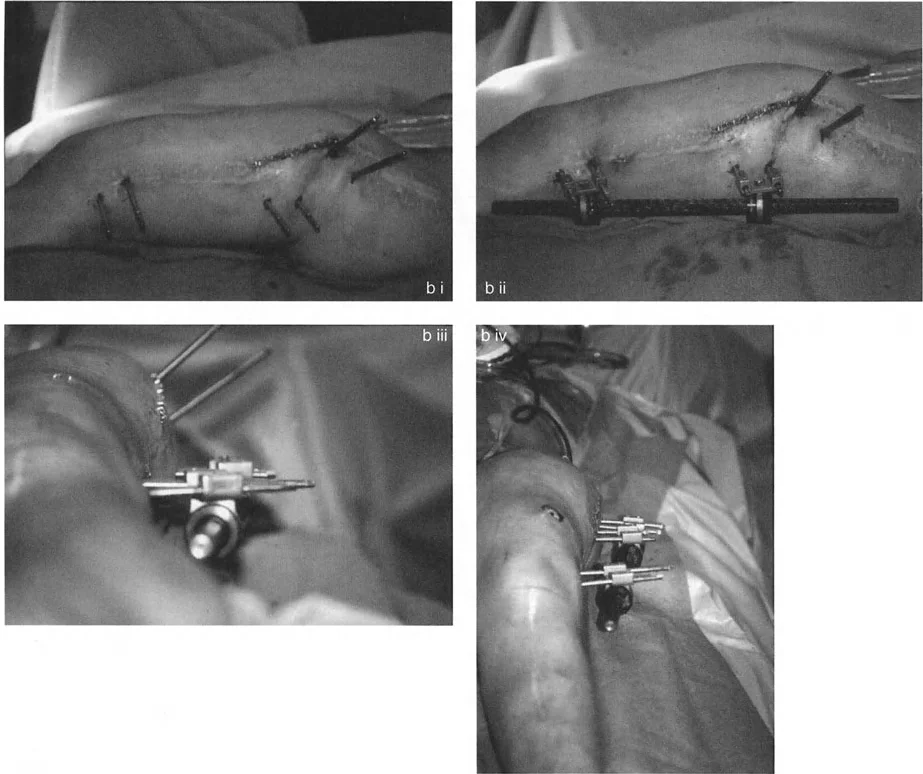

المثبتات الخارجية: أنواعها ودورها

تُستخدم أنواع مختلفة من المثبتات الخارجية لتطبيق مبادئ بالي وإليزاروف:

- مثبتات إليزاروف الدائرية الكلاسيكية: تتكون من حلقات معدنية متصلة بالعظم بأسلاك رفيعة، وتسمح بتصحيح متعدد المستويات.

- المثبتات أحادية الجانب (Monolateral Fixators): تتميز بقضيب واحد يمتد على طول الطرف، وتستخدم غالبًا للتصحيحات الخطية أو الزاوية البسيطة.

على العكس من ذلك، إذا تم استخدام دبابيس نصفية (مسامير شانز)، فإنها تقيد العظم بطبيعتها بالحلقة. نظرًا لأن الدبابيس النصفية هي أذرع صلبة (مثبتة من طرف واحد بالحلقة ومغروسة في العظم من الطرف الآخر)، فإنها لا تسمح للعظم بالانزلاق على طول محور السلك. هذا يجعل أسلاك الزيتون غير ضرورية للترجمة في منشآت الدبابيس النصفية، ولكنه يتطلب من الجراح التأكد من أن الدبابيس النصفية قوية بما يكفي (عادةً دبابيس بقطر 5 مم أو 6 مم مطلية بهيدروكسي أباتيت) لتحمل لحظات الانحناء الناتجة عن الترجمة.